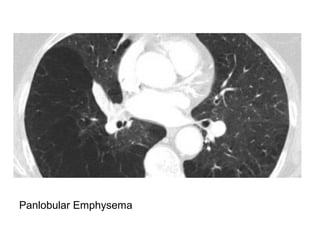

Centrilobular Emphysema

Panlobular Emphysema